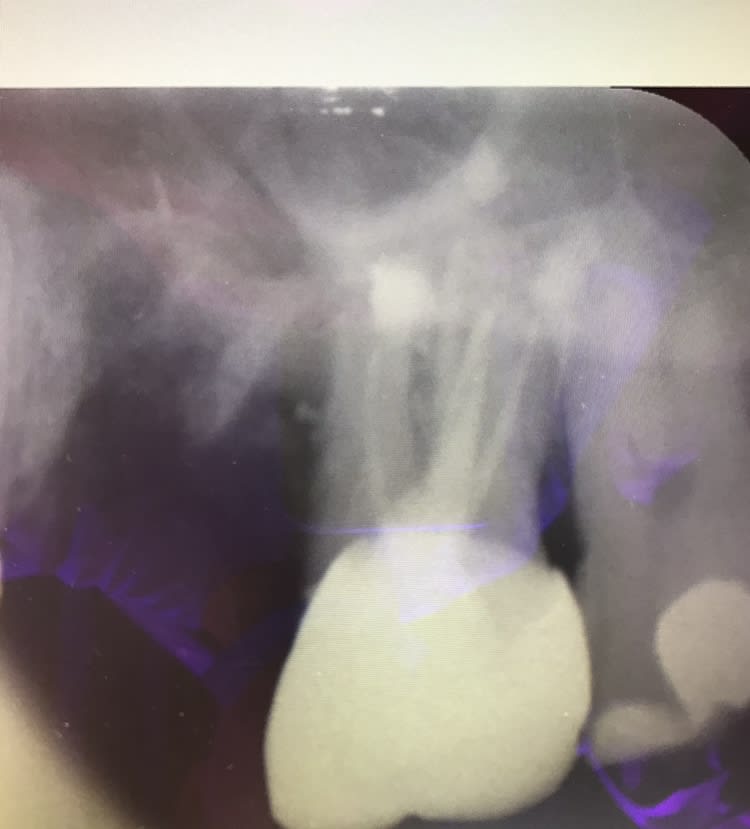

Bon allez je vous donne la solution :)

Ici La 6 ne pouvait pas être conservée (coupe scanner). Par contre la 7 oui . Obturation à rétro de la 7 et j’ai viré la 6. 6 mois après plus aucune douleur. J’attends encore 6 mois et je mettrai un bridge après avoir retraité la 5. Pendant ce temps je mets des implants de l’autre coté le temps que ces 6 mois s’écoulent.

Donc avec une bonne dose de volonté peut-être que ta 6 est conservable. Sinon l’ implant ça n’est également absolument pas une mauvaise solution pour ta 6.